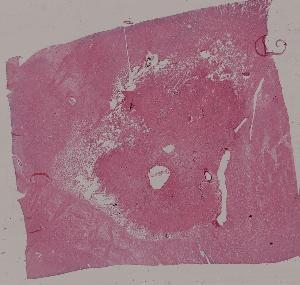

1.心肌褐色萎缩心肌肥大

2.肾曲管上皮混浊肿胀

3.肝细胞脂肪变性

4.脾包膜玻璃样变

5.血管壁纤维样坏死

6.肝细胞凝固性坏死

7.脑液化性坏死

10.肝淤血

11.淤血性肝纤维化

12.急性肺淤血

13.慢性肺淤血

14.混合血栓

15.机化血栓

16.肾贫血性梗死

17.肺出血性梗死

18.假膜性肠炎

19.蜂窝织性阑尾炎

20.肺脓肿

21.慢性扁桃体炎

22.慢性宫颈炎

第一页